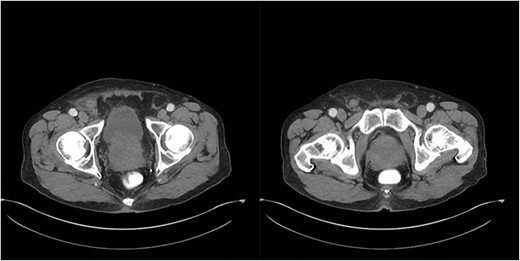

An 81-year-old male with a past medical history of childhood repair of cardiac septal defect presented to our emergency department (ED) with a two-day history of vague abdominal pain that migrated to his right groin with an associated non-reducible right groin mass. The non-reducible groin mass persisted, and his pain progressed that prompted him to come to the ED. Clinical examination revealed a firm, tender and irreducible right inguinal mass. The remaining clinical and laboratory tests were normal. Contrast-enhanced computed tomography (CT) of the abdomen and pelvis was performed. CT presented an acute appendicitis within a right inguinal hernia and a dilated appendix, measuring 13 mm in diameter and demonstrated periappendiceal fat stranding with no evidence of rupture (Figs 1–3). Patients’ history, physical exam and imaging findings were consistent with the preoperative diagnosis of an Amyand’s hernia with acute appendicitis. It was determined the patient will require operative intervention.

Coronal CT abdomen with oral contrast showing a dilated appendix periappendiceal fat stranding within a right inguinal hernia and no evidence of rupture.